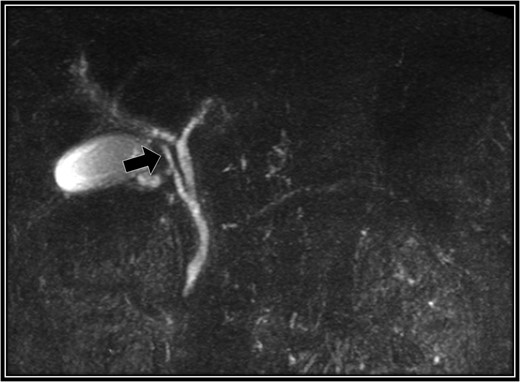

The patient was placed in supine position. Initially, intracorporeal procedures were performed in the laparoscopic view through four trocars (one 12-mm port and three 5-mm ports). We considered using intraoperative cholangiography to explore the right accessory hepatic duct. We incised the serosa by the neck of the gallbladder, used the Rouviere sulcus as a landmark, and peeled off the Calot triangle near the gallbladder. Subsequently, we identified the cystic artery and isolated it. Then we identified the cystic duct, and we inserted a cholangiography tube into it. The intraoperative cholangiography image showed that the right accessory hepatic duct branching from the cystic duct dominated an anterior segment of the right hepatic lobe (Fig. 3). Next, we isolated the cystic duct while preserving the right accessory hepatic duct. We resected the gallbladder. The total operating time was 125 min, and the intraoperative blood loss was minimal. Since the patient's postoperative course was uneventful, he was discharged 4 days later. We performed drip-infusion cholangiography-CT (DIC-CT) 48 days postoperatively. The DIC-CT scan demonstrated that the right accessory hepatic duct was intact, and it dominated an anterior segment of the right hepatic lobe (Fig. 4).

Intraoperative cholangiography image. The right accessory hepatic duct branching from the cystic duct (white arrow) dominates an anterior segment of the right hepatic lobe.